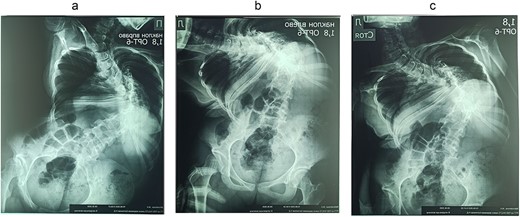

On the preoperative anterior–posterior X-ray, the Cobb angle was 110°; violation of frontal balance—13 cm (Fig. 2).

The rigidity of the scoliotic arch is noted on functional X-rays and on stretching (Fig. 3).